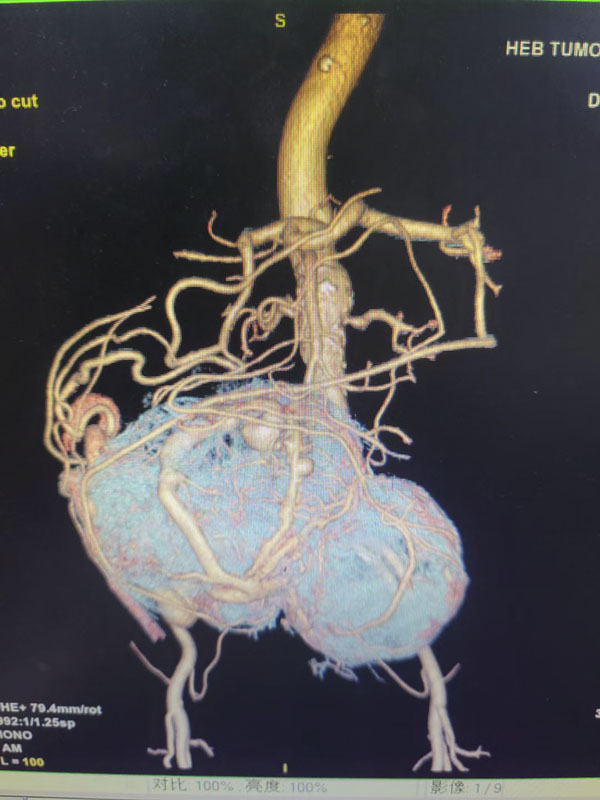

患者为一名72岁女性,今年4月体检时发现腹盆腔存在巨大肿瘤,且膀胱、直肠出现压迫症状,在外地诊治无果后前往我院外三科就诊,由李勇教授收治入院。经检查发现,患者中下腹可触一质硬、边界不清、不活动的肿物,病理结果考虑孤立性纤维瘤。CT影像显示,肿物长径约20cm,与肠系膜血管、髂血管、右侧输尿管、膀胱、子宫等组织器官关系紧密,同时CT血管三维重建显示肿瘤表面布满迂曲粗大的血管,肿瘤血供极为丰富,手术难度和风险极大。

手术当日,在麻醉科、手术室、输血科的协助配合下,泌尿外科张晓宇主治医师先行双侧输尿管D-J管置入术,介入科医师行经皮腹腔干、脾动脉、胃十二指肠动脉、肠系膜上动脉血管造影,在反复确认目标血管后,李智岗主任医师与杨光主任医师、李亚洲主治医师协作成功阻断肿瘤血供。随后,李勇教授、刘羽主任医师、夏宇翔主治医师进行剖腹探查,发现肿瘤表面布满粗大迂曲的血管,同时肿瘤呈囊实性,与周围组织分界不清,占据整个中下腹及盆腔。髂血管、肠管、膀胱、输尿管及子宫均呈不同程度受压。肿瘤停止供血后虽出现退缩表现,但分离过程中仍在出血,术中多次予以输血、止血。经过4小时的艰苦奋战,手术在我院专家团队“稳、准、快”的操作和入路的精准选择下顺利完成。